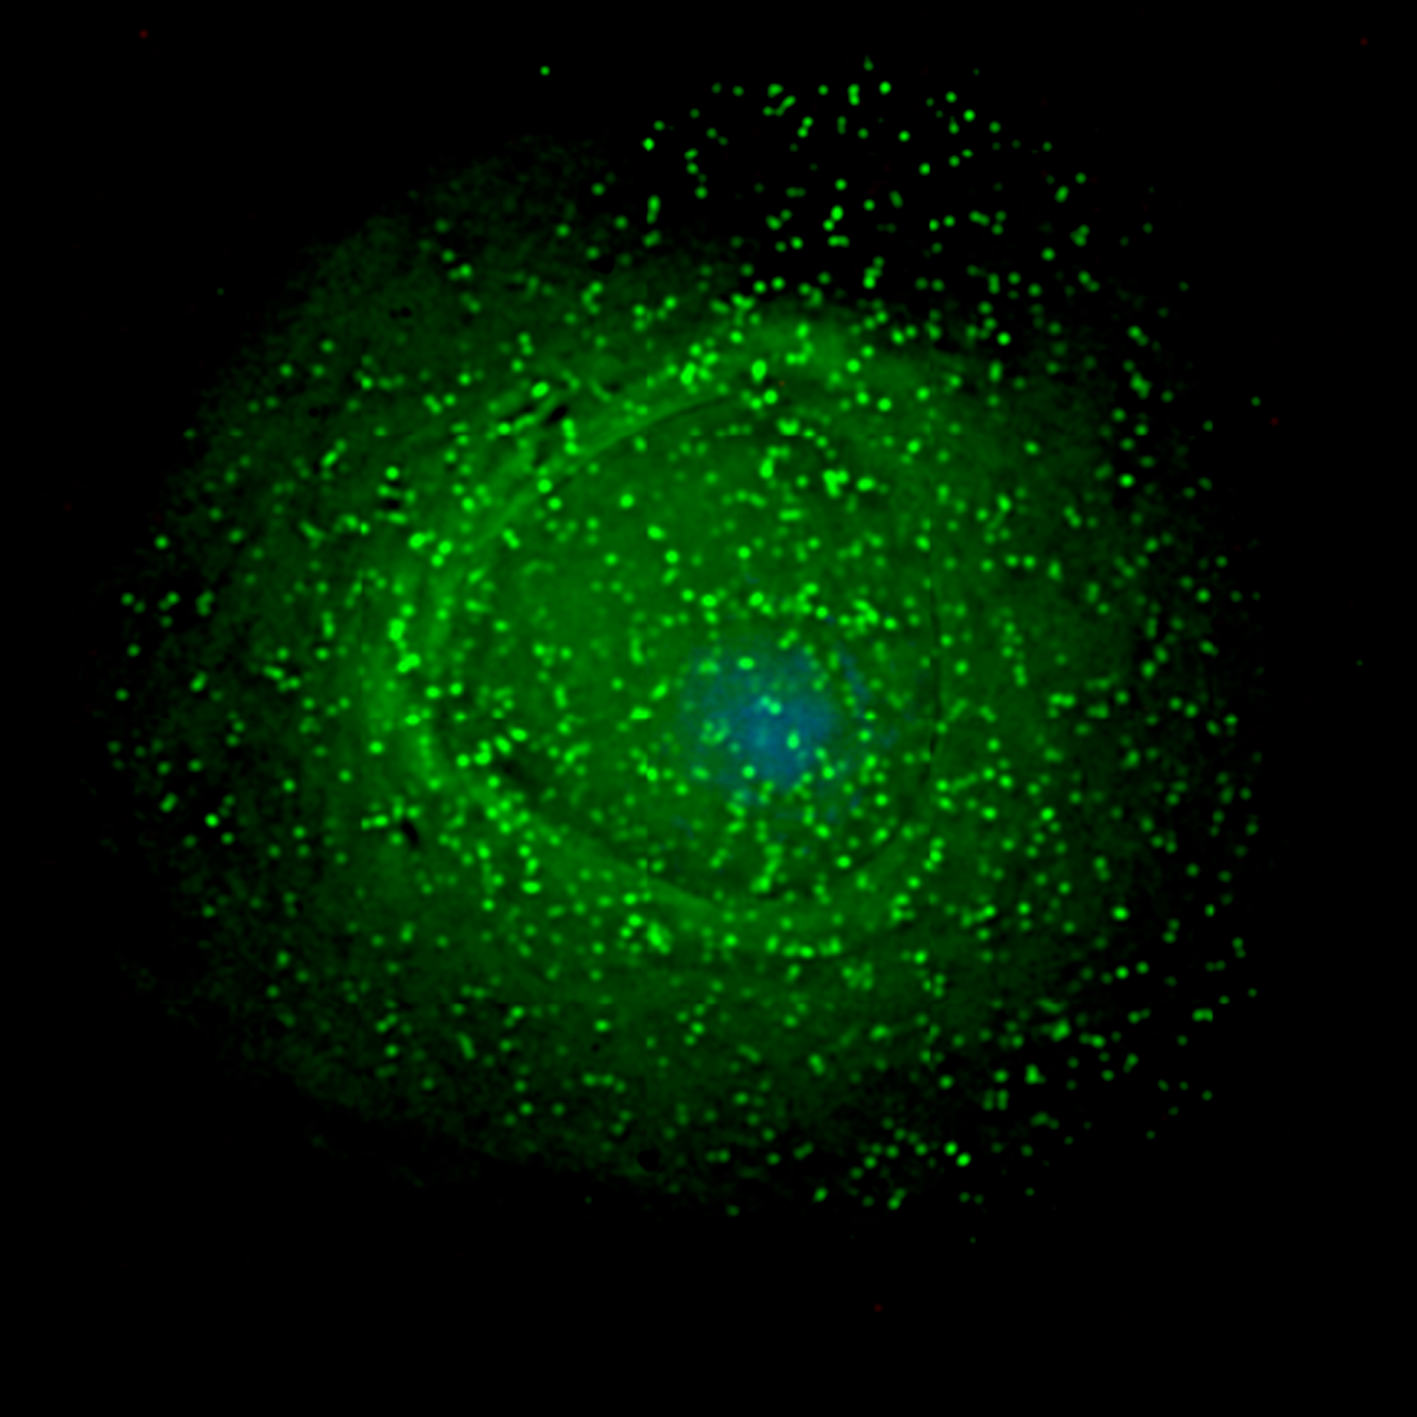

They found that people who produced bnAbs had more autoantibodies (antibodies against one’s own cells), fewer regulatory CD4 T cells, more memory T follicular helper cells and high PD-1 expression on Tregs.